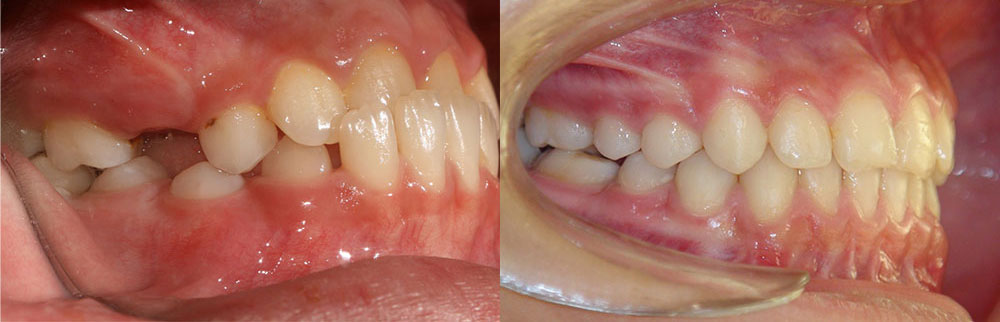

ارتودنسی دندان قبل و بعد، توسط پروفسور جمیلیان

برای دیدن نمونه کارهای ارتودنسی بیشتر می توانید به گالری تصاویر قبل و بعد ارتودنسی مراجعه کنید. در این قسمت تعداد بیشتری از این نمونه کارهای ارتودنسی دندان و فکین را مشاهده خواهید نمود. بسته به ناهنجاری فک و دندان درمان های متفاوتی در نظر گرفته می شود. در اینجا عکس دندان هایی که نیاز به ارتودنسی دارند را مشاهده می کنید. ممکن است بیماری شما نیز شبیه به یکی از این موارد باشد. در این صورت می توانید بهبودی و درمان های موفق را در این قسمت به وضوح مشاهده نمایید.